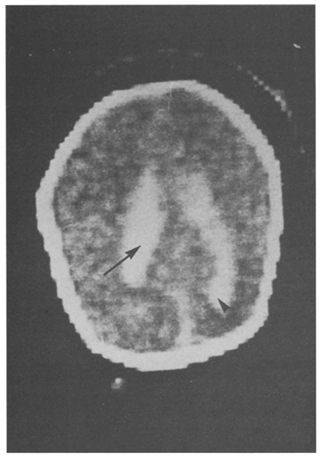

I first reviewed of the prognostic accuracy of severe ICH, making the point that there are 3 different types of haemorrhage which are all called grade 3. That is, those intraventricular haemorrhages that fill more than 50% of a lateral ventricle, those which acutely distend the ventricle, and those where there is blood in the ventricle and early post-haemorrhagic distension of the ventricle. These 3 types of grade 3 ICH may have different pathophysiology, and different prognostic implications, and, usually, it is not clear from a publication describing outcomes what they are including in their definition. The wording of the original system of classification by Lu-Ann Papile et al (based on CT scans) is somewhat ambiguous (“intraventricular hemorrhage with ventricular dilatation”), but the image was shown as an example in that publication, which I reproduce here, is of an ICH with acute haemorrhagic distension of the ventricle. In addition, bilateral and unilateral haemorrhages are put in the same category, and massive distension of the ventricles is lumped with those which have a minor degree of dilatation.